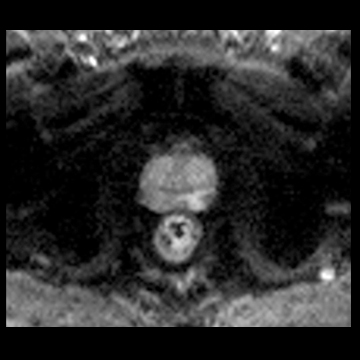

前立腺

高分解能T2

T2

RESOLVE, b=800

and ADC map,